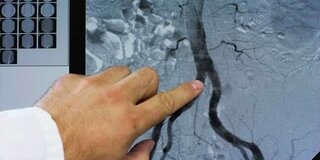

Lipoprotein (a): Ein Fett-Transportprotein

Ein hoher Lipoprotein (a)-Spiegel ist ein Risikofaktor für Gefäßerkrankungen

Lipoprotein (a) ist eines von vielen Eiweißen, die den Transport von Fetten durch das Blut ermöglichen. Es gehört zu den Low Density Lipoproteinen (LDL). Seine besondere Struktur erhält es durch eine Apolipoprotein-A-Kette. Hohe Lipoprotein-(a)-Werte können zusammen mit erhöhten LDL-Werten das Risiko für Gefäßkrankheiten von Herz und Gehirn erhöhen.

Fette aus der Nahrung können nicht einfach frei im Blut schwimmen. Sie werden als kleine Kügelchen von sogenannten Lipoproteinen transportiert ("Lipo-" heißt "Fett", "Proteine" sind Eiweiße). Lipoproteine sind also "Fett-Transporter". Es gibt verschiedene Lipoproteine, die nach Größe, Dichte und Zusammensetzung unterschieden werden. Lipoproteine mit einer hohen Dichte werden "High Density Lipoproteine" (HDL), oder auch "gutes Cholesterin" genannt. Lipoproteine mit einer niedrigen Dichte werden als "Low Density Lipoproteine" (LDL) bezeichnet und sind bekannt als "schlechtes Cholesterin".

Das Lipoprotein (a) ist ein Low Density Lipoprotein (LDL), das die Eiweißketten "Apolipoprotein B" und "Apolipoprotein A" enthält. Insbesondere von der Länge dieser Kette hängt es ab, ob der Lipoprotein-(a)-Wert im Blut hoch oder niedrig ist. Dieser Zusammenhang lässt sich nicht oder kaum durch die Ernährung, Sport oder Medikamente beeinflussen. Man hat festgestellt, dass Menschen mit hohen Lipoprotein-(a)-Werten ein erhöhtes Risiko für eine Herzgefäßerkrankung oder einen Schlaganfall haben können.